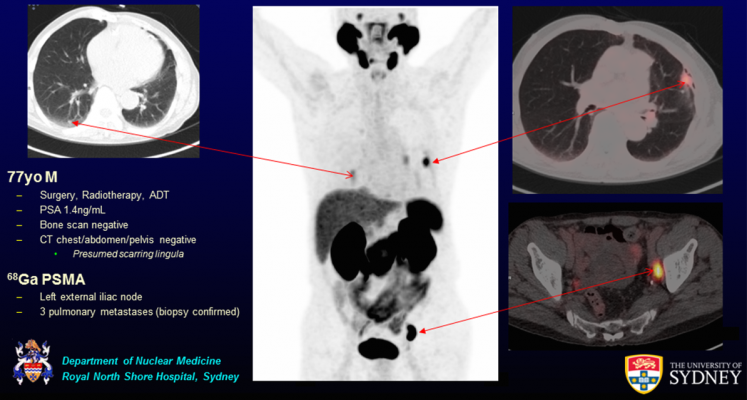

Prostate Pet Ct Targets More Cancer And Improves Patient Care Imaging Technology News

Psma Pet Ct Accurately Detects Prostate Cancer Spread National Cancer Institute